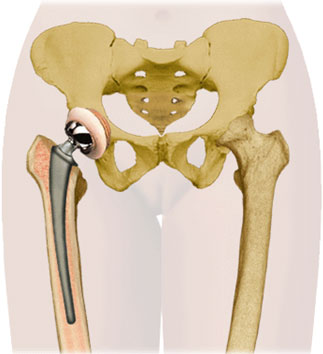

Total hip replacement (THR) involves replacement of both the ball (femur) and socket (acetabulum) of the hip joint. The femoral component is a modular one, consisting of a stem (made of metal such as cobalt-chrome or titanium) and head-neck (made of metal or ceramic). The acetabular component can be made of ceramic, metal or plastic (UHMWPE). The components are fixed to the parent bone by either bone cement (cemented hips) or by natural bone ingrowth/ongrowth over special porous or roughened surfaces (uncemented hips). Uncemented hips are costlier than cemented hips, and are supposed to have longer survivorship.

Diseases of the hip are commonly seen in young people, and hence, hip replacements should have high survivorship over 30 to 40 years. This has been achieved with the newer high-performance bearing materials like ceramic, oxinium and highly cross-linked poly. Hence, unlike knee replacements, hip replacements can even be done in adolescents, if required.

If only the ball (femur head) of the hip is affected, as commonly seen after hip fractures, only the femur head can be replaced in a partial hip replacement or hemiarthroplasty, and the native cup (acetabulum) is left untouched. The advantages of hemiarthroplasty over total hip arthroplasty are decreased surgical duration, morbidity and costs. However, the long term survivorship of hemiarthroplasty is limited (10-20 years), after which the native acetabulum wears out, and then it has to be converted into a total hip replacement. Hence, hemiarthroplasty is applicable only for elderly, low-demand patients, and total hip arthroplasty is the preferred surgery for younger patients (even if the acetabulum is healthy).